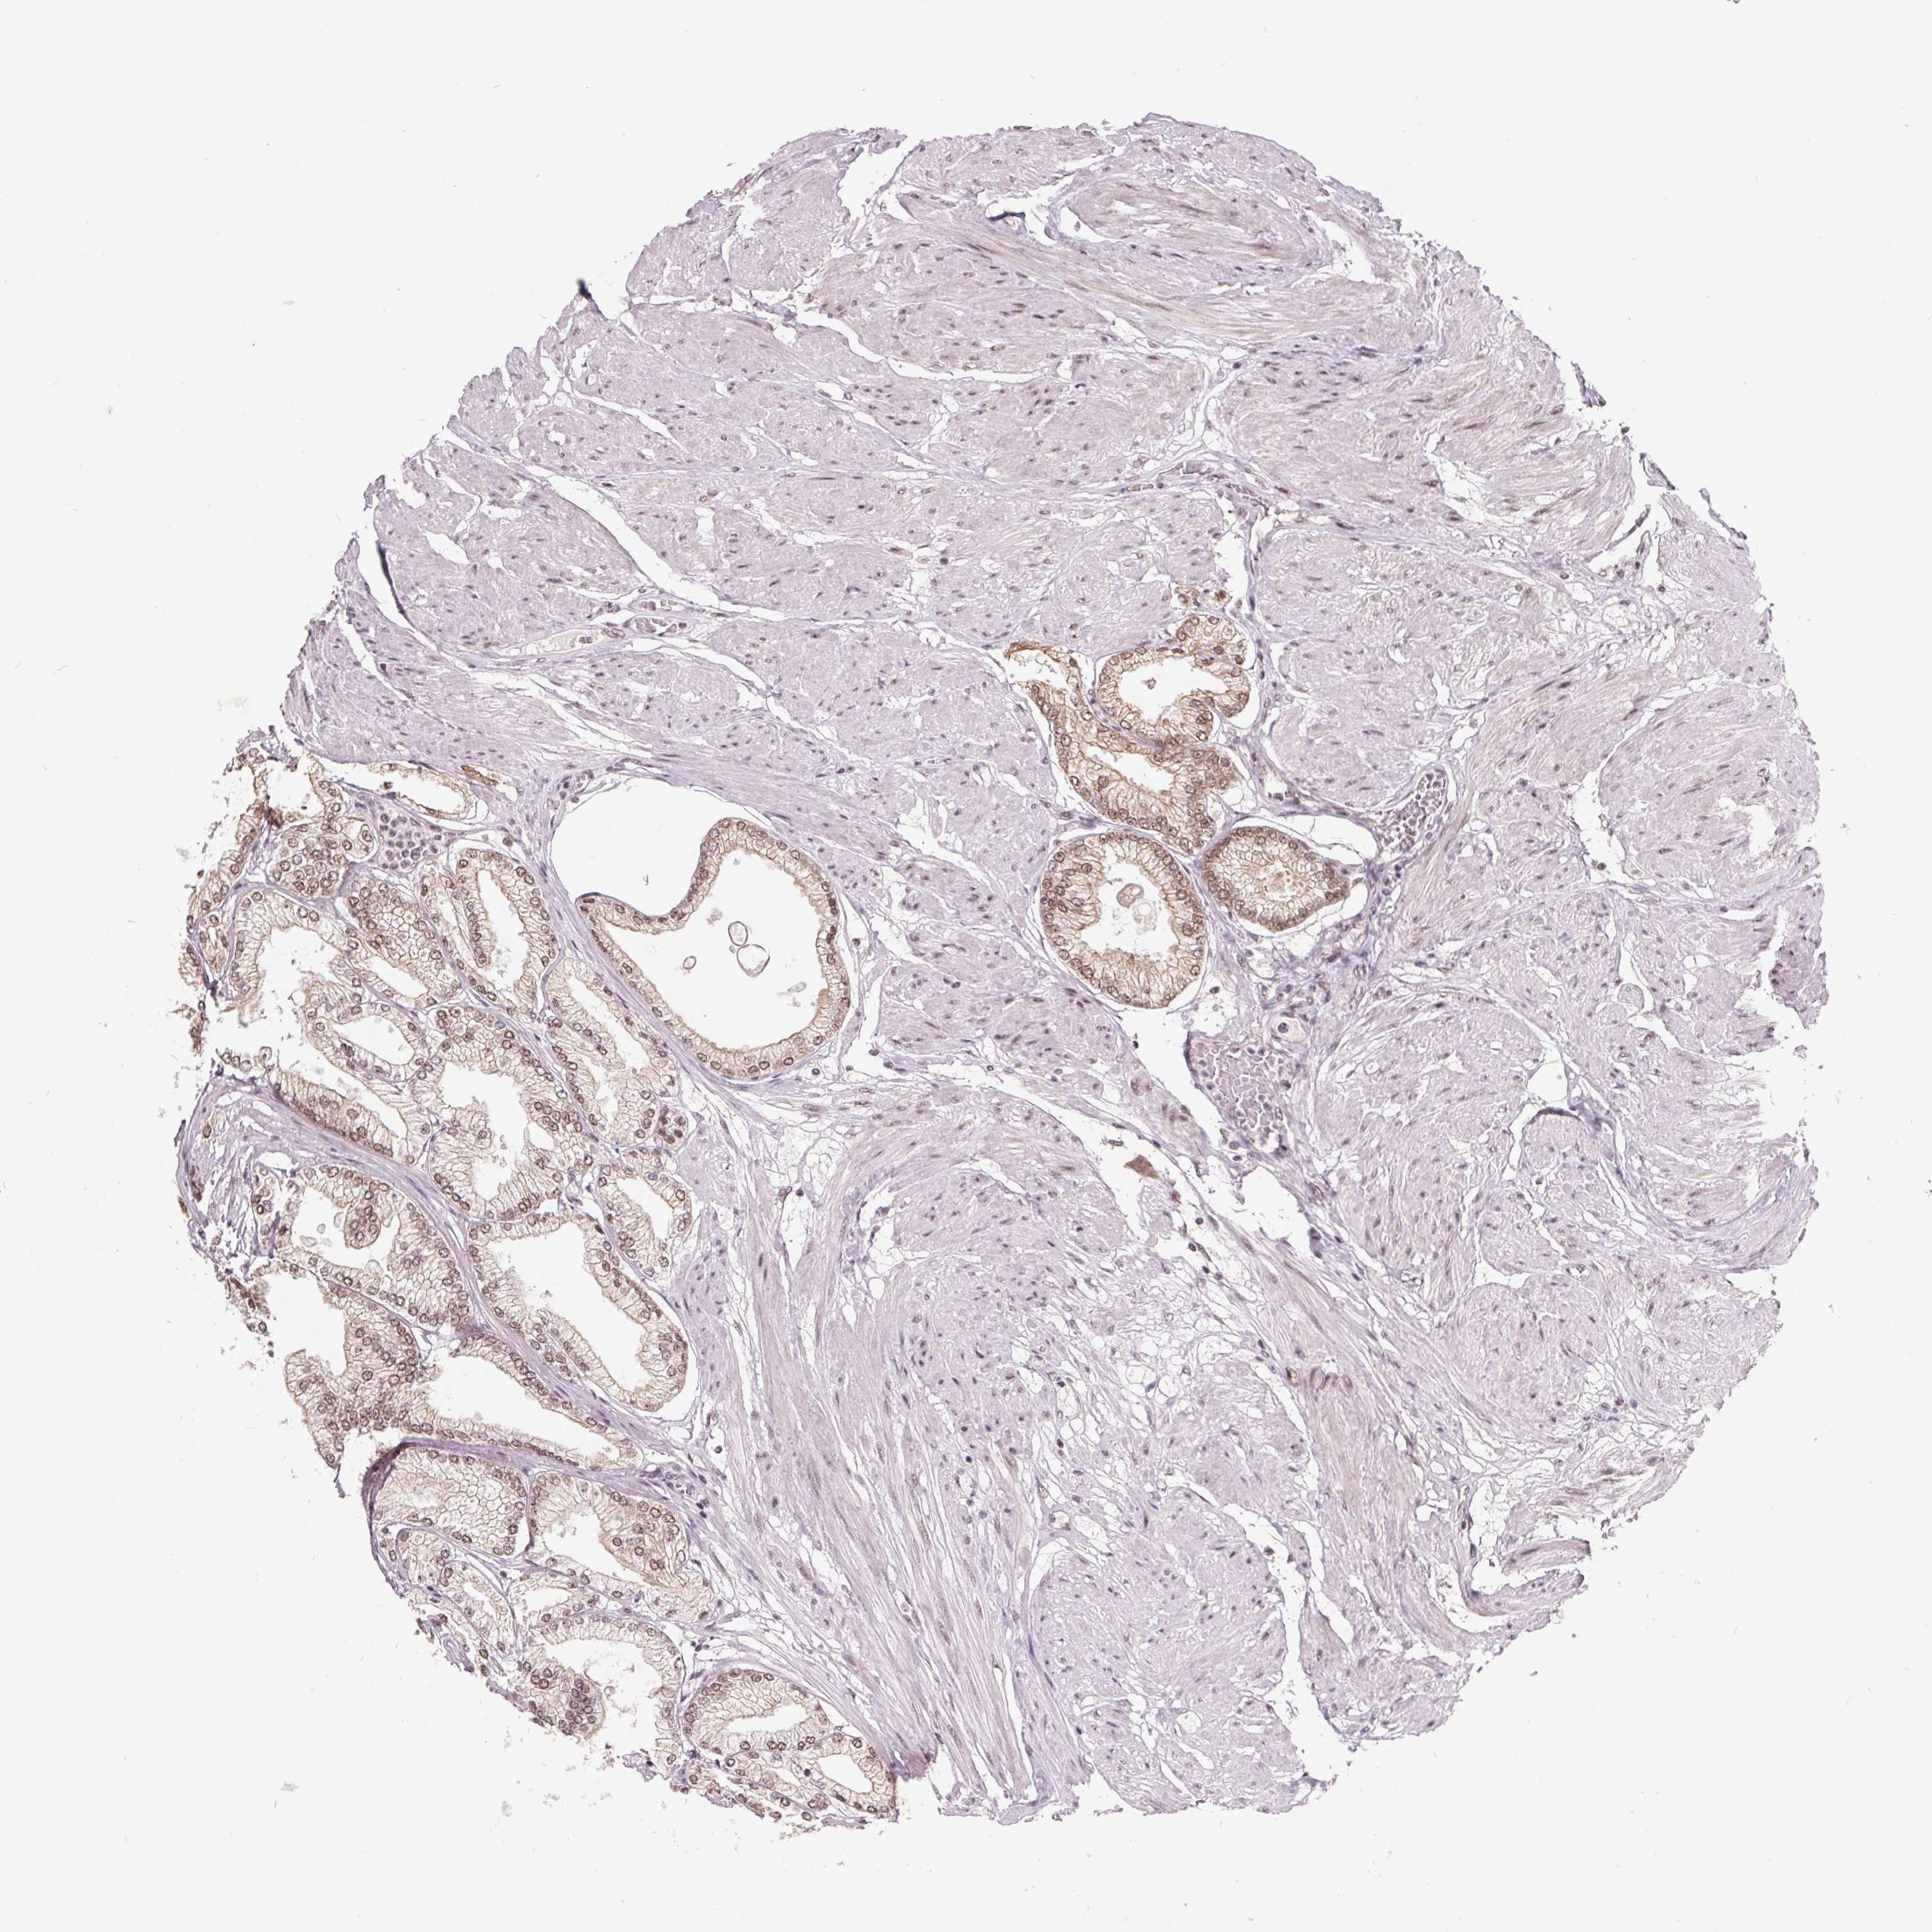

PROSTATE CANCER - Protein expressioni

A mouse-over function shows sample information and annotation data. Click on an image to view it in a full screen mode. Samples can be filtered based on level of antibody staining by selecting one or several of the following categories: high, medium, low and not detected. The assay and annotation is described here.

Antibody stainingi

Antibody staining in the annotated cell types in the current human tissue is reported as not detected, low, medium, or high, based on conventional immunohistochemistry profiling in selected tissues. This score is based on the combination of the staining intensity and fraction of stained cells.

Each image is clickable and will lead to virtual microscopy that enables deeper exploration of all samples and also displays staining intensity scores, fraction scores and subcellular localization as well as patient and tissue information for each sample.

Antibody HPA064854

Staining

High

Medium

Low

Not detected

Intensity

Strong

Moderate

Weak

Negative

Quantity

>75%

75%-25%

<25%

None

Location

Nuclear

Cytoplasmic/membranous

Cytoplasmic/membranous,nuclear

Adenocarcinoma, High grade

Adenocarcinoma, Medium grade

Adenocarcinoma, Low grade